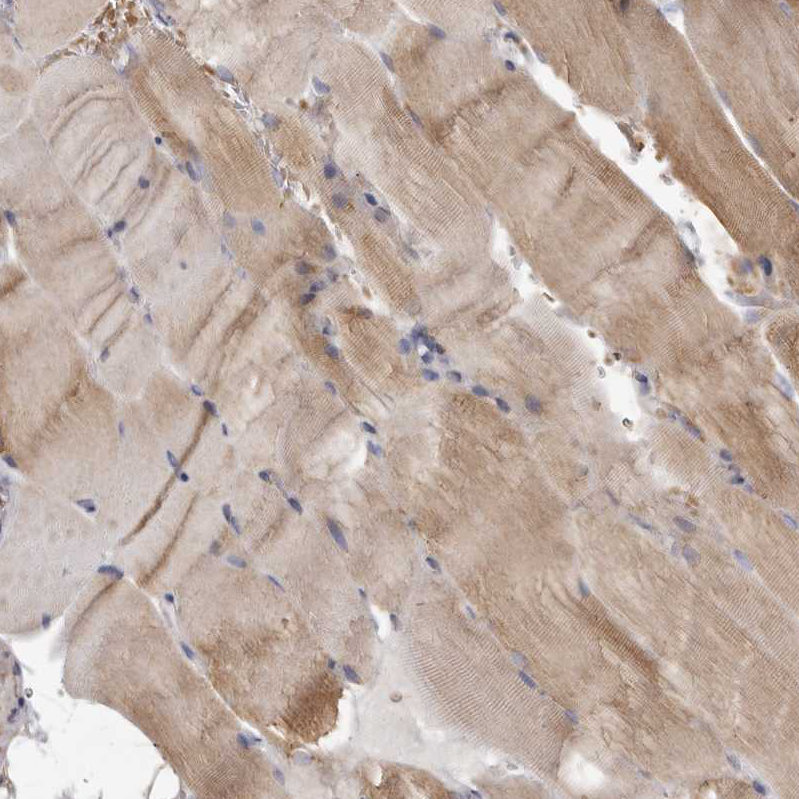

Immunohistochemical staining of human cerebral cortex, placenta, skeletal muscle and testis using Anti-MECR antibody HPA028740 (A) shows similar protein distribution across tissues to independent antibody HPA022018 (B).